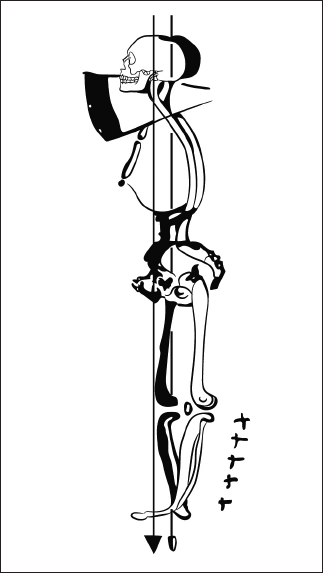

Патобиомеханика: возникают заднее смещение головы, наклон таза назад, избыточное сгибание в коленных суставах (рис. 21).

Рис. 21. Неоптимальная статика. Заднее смещение головы, наклон таза назад и избыточное сгибание в коленных суставах как результат нарушения формирования рефлекса разгибания.

Тесты для диагностики нарушения

В положении лежа на животе необходимо прижать плечи к опоре и разогнуть голову, прижимая подбородок к шее. Далее, сохраняя это положение, поворачивать голову в разные стороны. Также необходимо оценить разницу в подъеме головы при ее повороте в каждую из сторон. Признаки нарушения: невозможность поднять голову при фиксированном подбородке или разница в объеме движения.